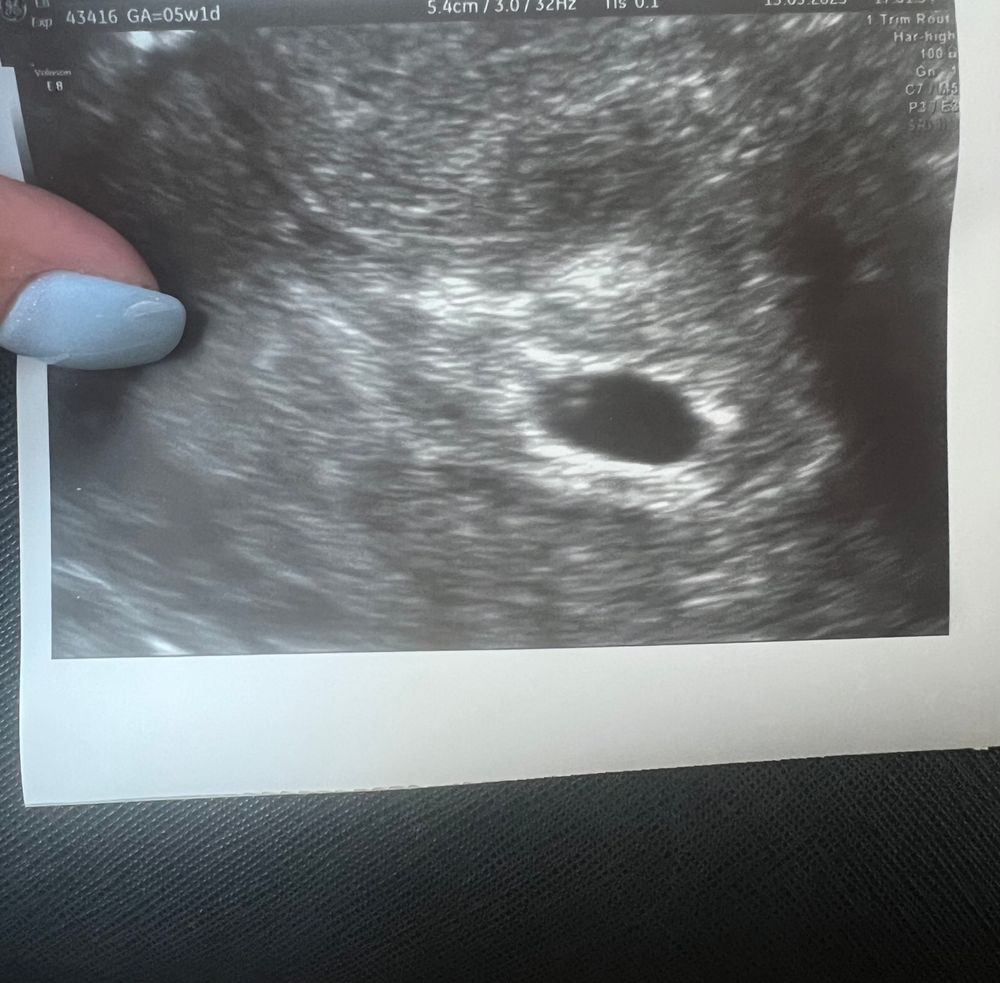

узи плодное яйцо 7 мм желточный мешок и эмбрион не визуализируются ,по размеру плодного яйца написали 5 недель и 6 дней беременности ,по календарю 5 недель ровно ,может у кого-то было такое есть ли шансы ?